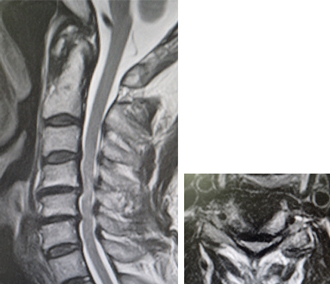

頚椎症性脊髄症のMRI。脊髄が高度に圧迫されています。